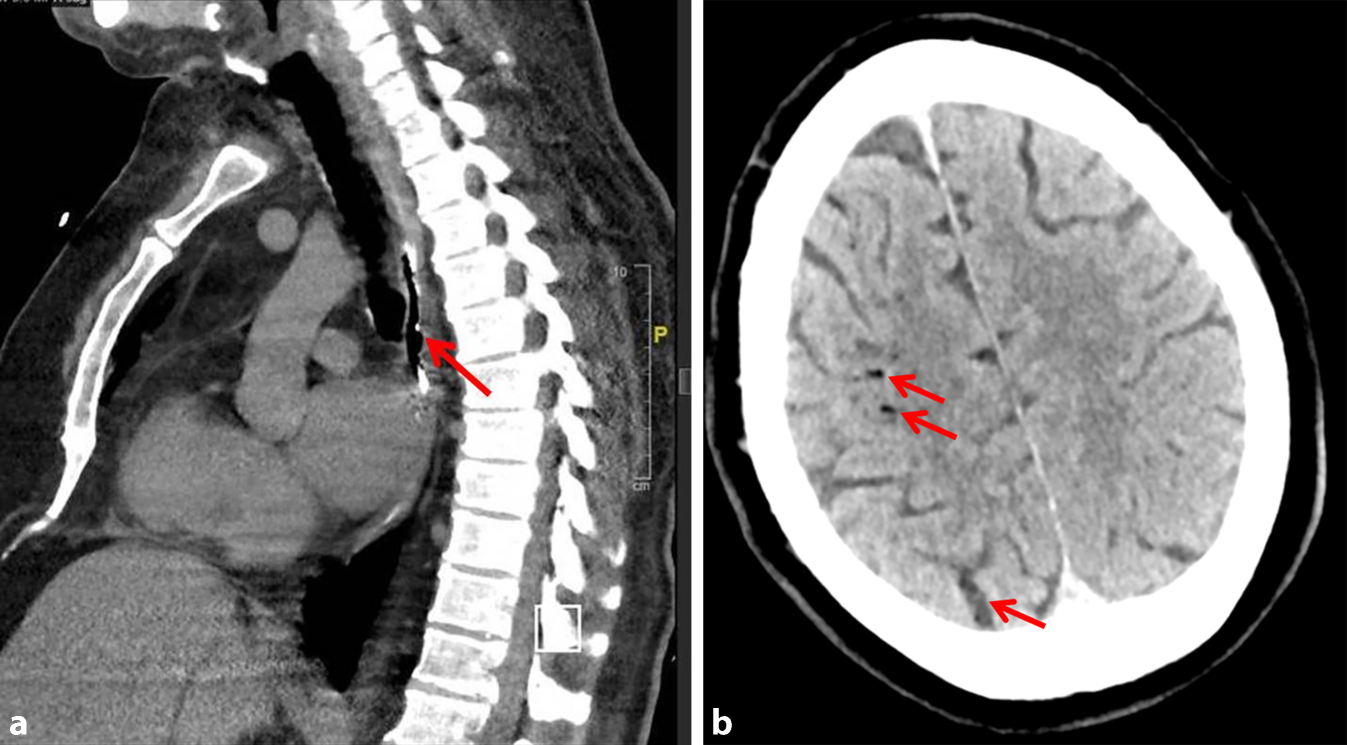

Eine empirische Therapie mit Piperacillin/Tazobactam und Caspofungin wurde begonnen und der Patient in das Universitätsklinikum Jena verlegt. Ergänzend erfolgte eine thorakale Kontrastmittel-CT, die mit dorsal des linken Vorhofs befindlichen Lufteinschlüssen (Abb. 1a) die Diagnose bestätigte.

Abb. 1

a Computertomographie des Thorax mit Lufteinschlüssen dorsal des linken Vorhofs (Pfeil), b kraniale Computertomographie: Darstellung multipler Lufteinschlüsse, rechts parietal sowie okzipital (Pfeile)

Eine stark wechselnde neurologische Symptomatik (schlaffe armbetonte Hemiparese links, Herdblick nach rechts, Feinmotorikstörung der kontralateralen Hand und eine latente rechtsseitige Hemiparese sowie Dysarthrie) führte zu einer erneuten CCT, die mehrere kortikale Lufteinschlüsse zeigte (Abb. 1b).

Wegen der Seltenheit der atrioösophagealen Fistel bleiben die Bewertung und Validierung von Strategien zur Reduzierung eine Herausforderung. Eine zielgerichtete und adäquate Therapie sollte immer im Einklang der verschiedenen Fachabteilungen erfolgen; individualisiert können unterschiedliche Ansatzpunkte gewählt werden. In einem rezenten Review evaluierten Povey et al. [1] Symptome, diagnostische Modalitäten und das Management der atrioösophagealen Fistel. Das Durchschnittsalter der Patienten betrug 61 Jahre, sie waren vornehmlich männlich (73 %), und die Begleitsymptome waren auch hier Fieber in 75 % und neurologische Dysfunktionen in 77 % der Fälle. Als mediane Zeit von Ablation bis zum Eintritt der Symptome wurden 21 Tage (Quartilsabstand: 12–28) beschrieben. Die empfindlichste Thoraxbildgebungsmodalität war die CT (n = 135/153; 90 %). Dies fanden auch Han et al. [7], in der in 68 % der Fälle die CT des Brustkorbes zwar die häufigste Diagnosemethode war, sie in 7 Fällen bei primär unauffälligem Befund jedoch wiederholt werden musste. Zu den eindeutigen Bildgebungsergebnissen gehörten freie Luft im Mediastinum (Inzidenzrate 81,73 %) und die Luftembolie des Gehirns (Inzidenzrate 57,53 %) [9]. Diese „klassischen“ bildmorphologischen Besonderheiten zeigten sich auch bei unserem Patienten. Dies sollte in dieser Kombination und der Vorgeschichte nach Pulmonalvenenablation zwingend an die Diagnose einer atrioösophagealen Fistel denken lassen. Bei 19 % der Patienten trat eine sofortige Verschlechterung bei Ösophagogastroduodenoskopien (ÖGD) auf [1]. Diese Manipulationen sollten in jedem Fall vermieden werden, da dadurch induzierte Luftembolien zu erheblichen neurologischen Schäden führen können. Die Sterblichkeit in der von Povey et al. betrachteten Patientenklientel war niedriger bei Patienten, die operiert wurden (39 %), im Vergleich zu endoskopischen Eingriffen (94 %) oder konservativer Behandlung (97 %). Patienten, bei denen eine Vorhofreparatur in Kombination mit einer Ösophagusreparatur oder Ösophagektomie durchgeführt wurde, überlebten mit größerer Wahrscheinlichkeit als diejenigen, bei denen eine Vorhofreparatur allein durchgeführt wurde (OR 6,97; p < 0,001). Die Isolierung des ösophagealen Aspekts der Fistel verlieh einen zusätzlichen Überlebensvorteil (OR 5,85; p = 0,02) [1].